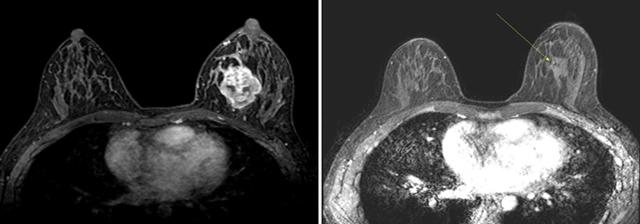

계적으로 여성은 3명 중 1명이 암에 걸린다고 합니다. 여성암 중 갑상선암 다음으로 두 번째로 높은 암이 유방암이라고 하는데, 중년 여성의 암 사망률로는 유방암이 1위라고 합니다. 유방암이란 유방에 나타나는 모든 악성 종양을 통틀어 말하는 것으로 보입니다. 유방암은 유방에 비정상적인 조직이 계속 자라거나 다른 장기에 퍼지는 위험한 병이라고 할 수 있습니다.